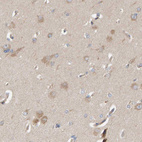

Immunohistochemistry analysis in human lymph node and pancreas tissues using HPA021669 antibody. Corresponding CCM2 RNA-seq data are presented for the same tissues.